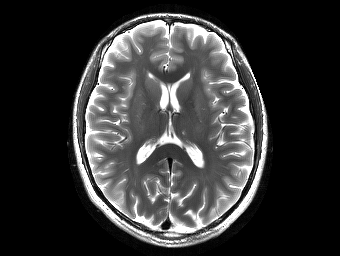

Brain MPRAGE. We used an MPRAGE sequence on a 3T scanner to acquire a T1-weighted human brain image using a 32-channel receiver array, as depicted in Fig. 1(a).